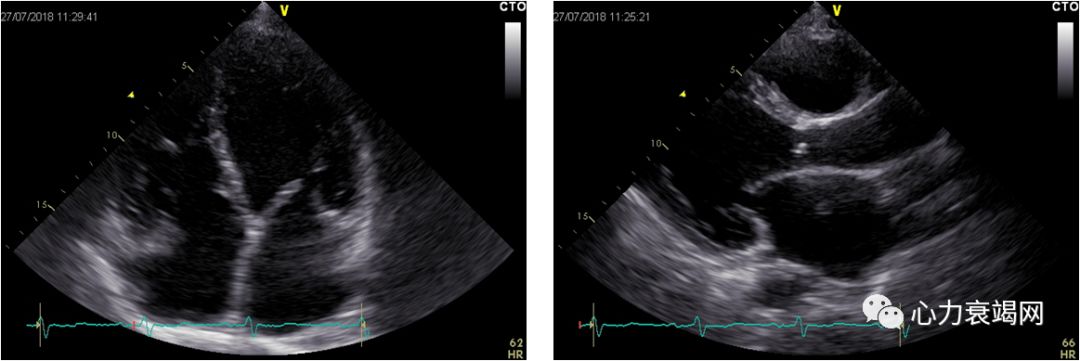

一、M型主要测值(单位mm):

名称 测量值 正常参考值

主动脉根部内径 31 20-37

左房内径 52 9-40

左室舒张末期内径 67 35-56

左室收缩末期内径 57 20-37

室间隔厚度 8 6-11

左室后壁厚度 7 6-11

二、二维超声心动图描述:

1. 全心增大,以左心增大为主。

2.左室壁不增厚,静息状态下左室壁收缩活动普遍减弱,LVEF低下。在心尖切面观中用双平面改良Simpson法测得LVEF约26%。

3.各心瓣膜未见明显增厚,开放不受限。

4.三尖瓣瓣环收缩期位移约17mm。

诊断意见:全心增大,心功能不全;中度二尖瓣关闭不全;中度肺动脉高压伴中重度三尖瓣关闭不全